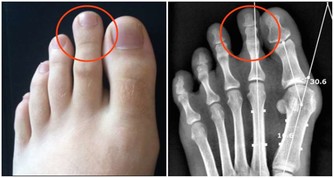

1、護好雙腳:足部保暖是養腎的一種方法,每天用熱水泡泡腳,在做一些簡單的按摩,睡覺時不要將雙腳正對空調或電扇,不要赤腳在潮濕的地方長期行走。